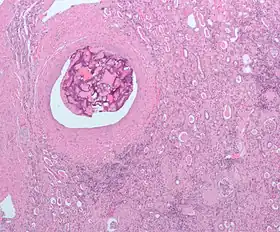

Foreign material in a blood vessel due to an embolization procedure.

Talcosis of the lung due to intravenous drug use. H&E stain.